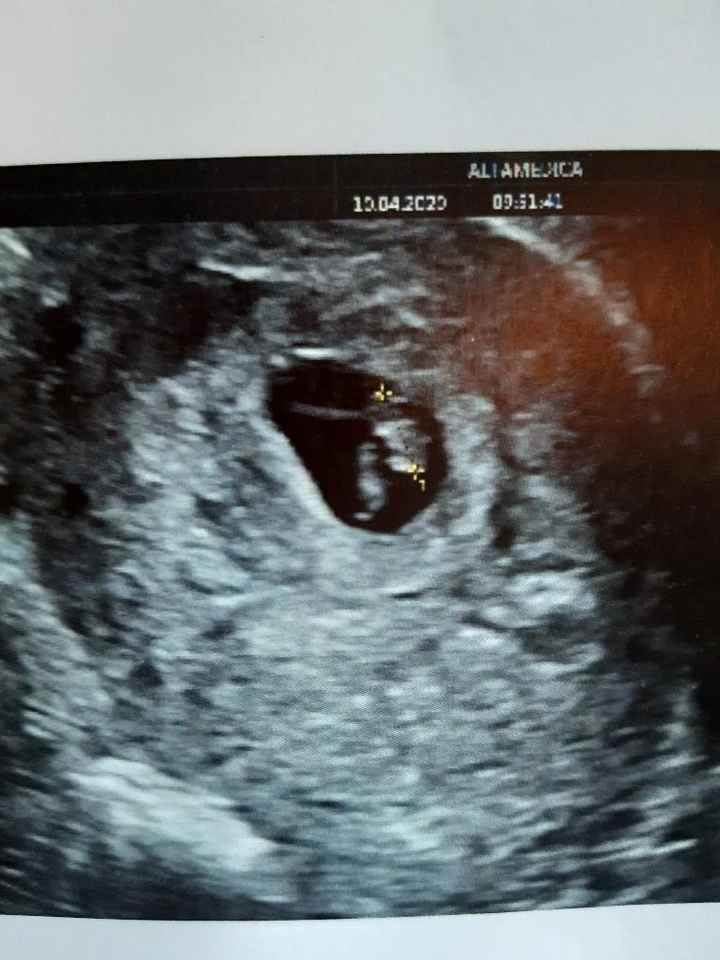

Oggi ho fatto la traslucenza nucale e la dottoressa mi ha detto che il fagiolino era in posizione impeccabile,tanto che il tubercolo si vedeva benissimo e mi ha detto femmina al 100%. Io già da ramzi avevo predetto femmina, ma aspettavo di snetirmelo dire. E così, com'è stato per il primo figlio dove secondo ramzi era maschio, e maschio è stato, anche stavolta ci ha preso 😍 siamo felicissimi, la bimba sta alla grande e si chiamerà VITTORIA. 🌺🌺🌺🌸🌸 Vi lascio l'eco di oggi dove si vede benissimo il tubercolo parallelo alla spina dorsale. Un bacio